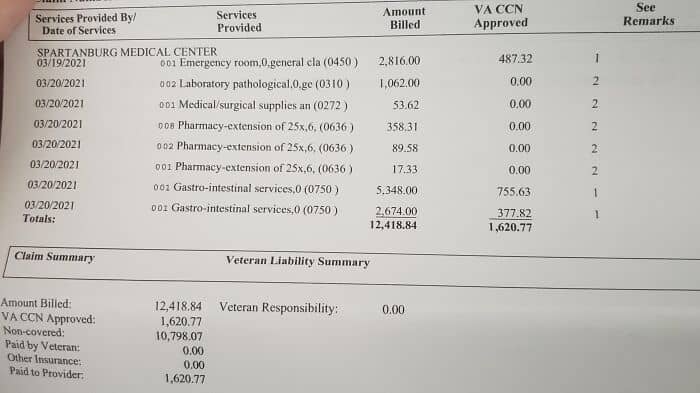

#48 My Visit To The ER As A Veteran. This Is What Universal Healthcare Would Look Like

#49 This Is What $10,000 Looks Like Under The American Health Care System